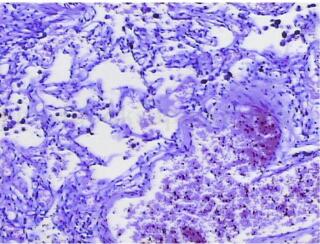

左肺下叶内基底段肺隔离症(图2)

图2 病变内见动脉管壁结构,其内大量弹性纤维,厚壁动脉管壁旁可见肺组织,组织内炎细胞浸润,血管充血